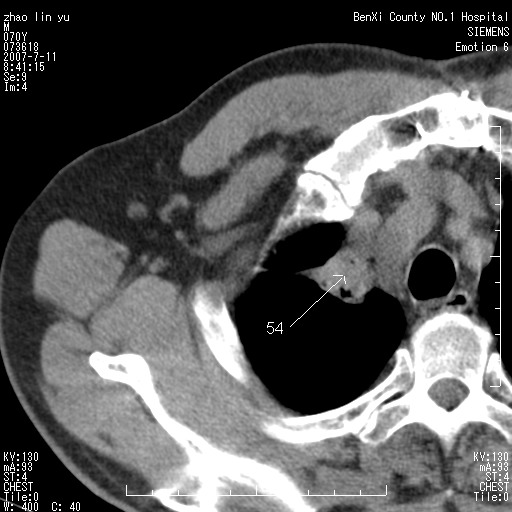

以下是引用王靖旗在2007-7-10 17:12:00的发言:[br] 男、70、咳嗽两个月,半年前换瓣手术,胸片未见异常,于昨天行x片发现右肺上野大片影,行ct扫描,这里是减薄图像,余肺正常。明天晚上会有增强扫描片,到时我会上传。[br][br] 冠状位请大家细看,应该是有意义的,[br][br] 请大家先看平扫发表意见。[br][br]

以下是引用zhangzhongshou在2007-7-10 21:43:00的发言:[br]右肺上叶周围型肺癌,以孤立型细支气管肺泡癌可能性大。